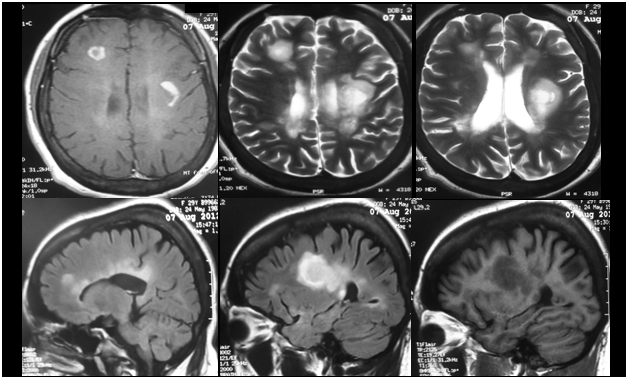

Cranio-cervical MRI revealed T1-iso/hypointense, T2- and FLAIR hyperintense demyelinating lesions located in the right side of bulbus and pons, and in the bilateral periventricular white matter; large demyelinating lesions with marked contrast enhancement in the left supraventricular white matter and right frontal subcortical white matter; thinning in the corpus callosum and a demyelinating lesion in the dorsal of the spinal cord at C3 vertebral level. In the CSF analysis, IgG index was 0,76 (0,28-0,66) and oligoclonal band was detected. There were 8-10 erythrocytes and 10 leucocytes in the CSF microscopy. There was no atypical cell. Visual evoked potentials and sensory evoked potentials were in normal ranges. The patient was diagnosed as multiple sclerosis. Intravenous methylprednizolone 1 g/day was given for 5 days. The deficits disappeared in the follow-up of the patient. Immunomodulatory therapy was started.

Figure 2 MRI of the patient revealing contrast-enhancing (upper left), T2-hyperintense (upper middle and right), FLAIR-hyperintense (lower left and middle) and T1-hypointense demyelinating lesions.